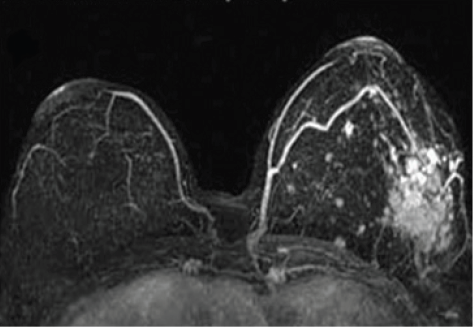

DCE-MRI is a routine screening tool for breast cancer (Figure 6). Some research groups report using ultra small particle iron oxides (USPIO) to detect involved lymph nodes as small as 2 mm on T2*-weighted MRI pulse sequences. This information can be used during treatment planning to spare uninvolved lymph nodes, has the potential to support conservative breast surgery and more targeted radiation therapy, thereby reducing the side effects of radiation and surgery [63,64].

Figure 6:Base-of-tongue tumor imaged with different techniques. Left: CT simulator; Center: PET-FDG; Right: T1-weighted postcontrast MRI.